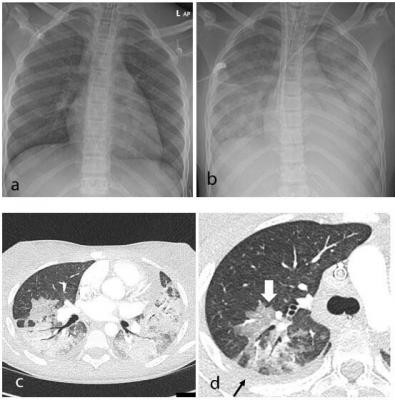

Serial Computed Tomographic Findings And Specific Clinical Features Of Pediatric Covid 19 Pneumonia A Case Report